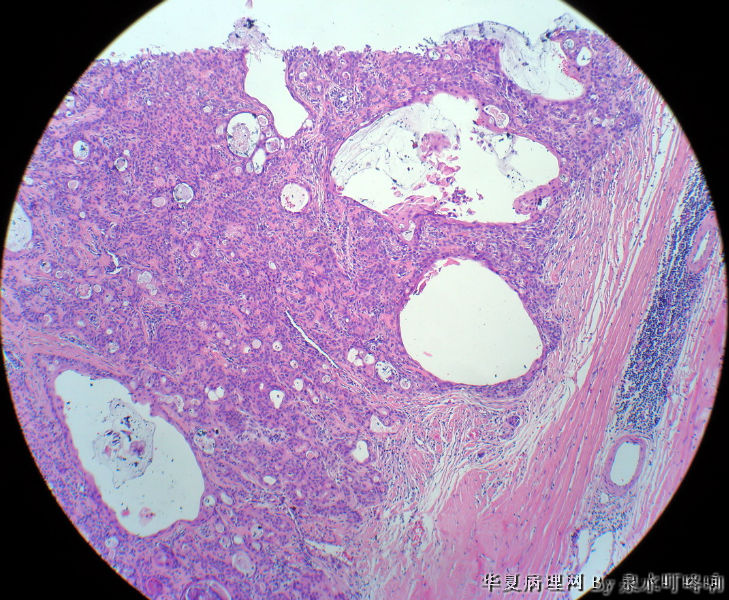

左腮腺肿物

女,38岁,左耳下方肿物,临床诊断:左腮腺肿物。

大体:灰白肿物一个,大小约4×3.5×3厘米,切面灰白,质略软,可见多发囊腔。

(左腮腺)多形性腺瘤

多形性腺瘤(粘液软骨样区域+上皮成分)

瘤组织由多种上皮成分(腺上皮+肌上皮+鳞化上皮)及黏液软骨样基质构成,多形性腺瘤可以囊性变,多结节状分布。

多形性腺瘤,肌上皮、腺上皮增生,鳞化、粘液背景

1、境界清楚

2、两种类型细胞:导管上皮+肌上皮,肌上皮与周围间质有融合现象。

3、伴有角化的鳞状分化。

4、间质:软骨粘液样间质+弹力纤维。

综上:多形性腺瘤。